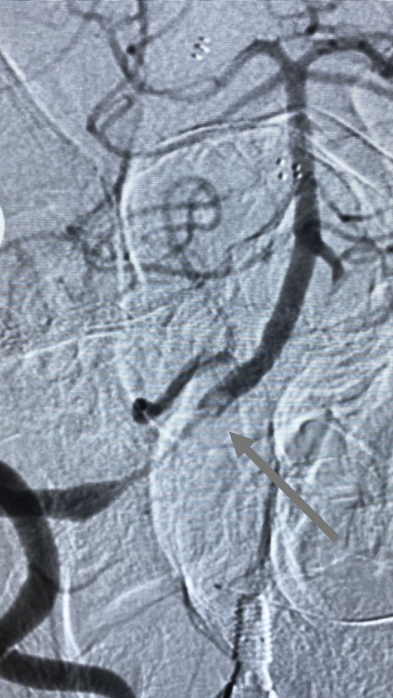

DSA显示ICAO

微导管造影证实MCAO

手术过程

中间导管配合在长鞘和小球囊的配合下穿过迂曲夹层的颈内动脉。

微导管微导丝穿过夹层段,4.0×20mm球囊再次反复贴附夹层段,促进内膜贴壁。

造影观察,管腔狭窄较前好转,血流状态稳定,结束手术。

2018-3-9 日复查CT及CTA,夹层自愈过程中,无栓塞,转康复科行康复训练。